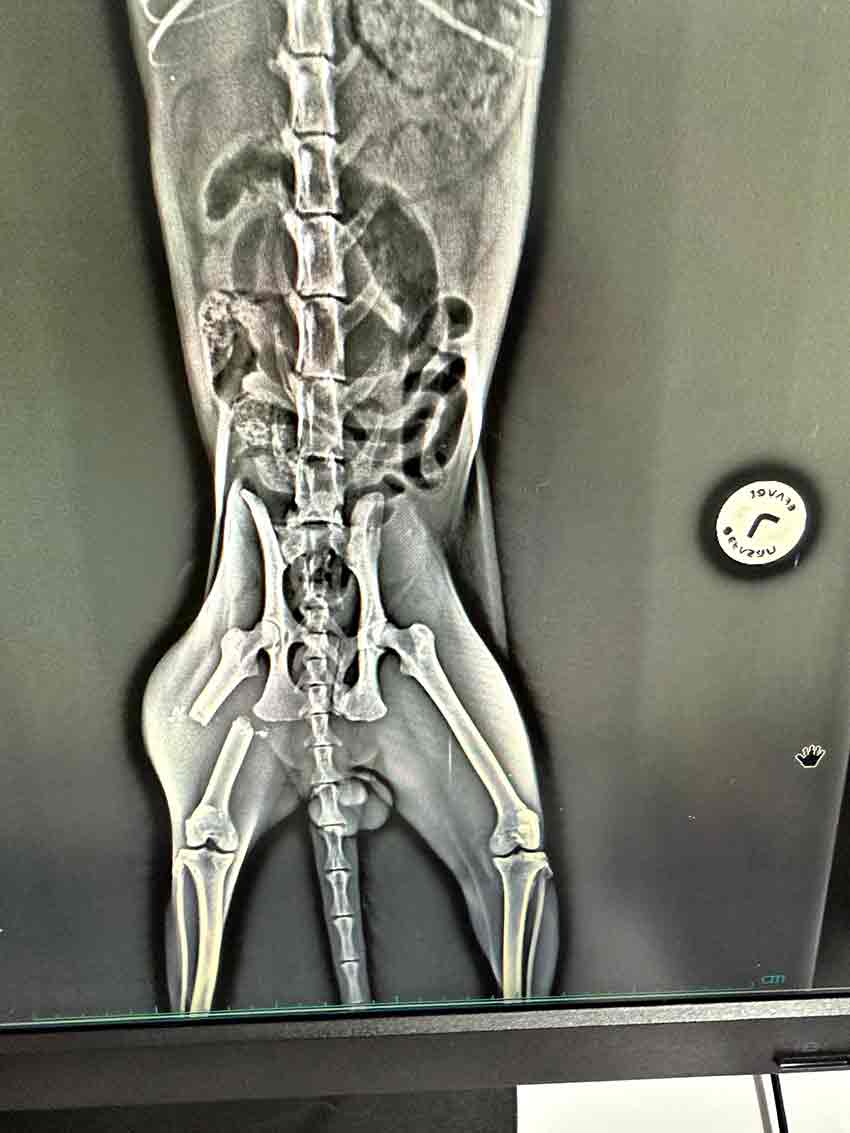

Zonguldak'ta evin balkonundan düşen kedi yaralandı. Ameliyata alınan kedi tedavisi yapılarak sağlığına kavuşuyor.

Veteriner Hekim Koç, Havaların ısınmasıyla birlikte, evi havalandırmak amacıyla camlar ve kapılar açılıyor. Ancak bu durum, ne yazık ki kedilerimizin camdan atlaması ya da kapılardan kaçmasıyla sonuçlanabiliyor. Kaçan kediler sokakta travmaya maruz kalabiliyorlar. Camdan atladıklarında ise travmalar çeşitli şekillerde ortaya çıkabiliyor; kırıklar hatta Allah korusun ölümle sonuçlanabilecek kazalar meydana gelebiliyor. Bu nedenle yaz mevsiminde camlar açılırken kontrollü olunması ya da sineklik kullanılması gerektiğini, her yıl olduğu gibi bu yıl da yeniden hatırlatıyoruz. Bu hastamız da travma sonucu yani bir trafik kazası nedeniyle kaçamamış ve maalesef kırık oluşmuş. Yaptığımız ameliyatla kırık başarıyla tedavi edildi. Şu an genel sağlık durumu iyi şeklinde konuştu.